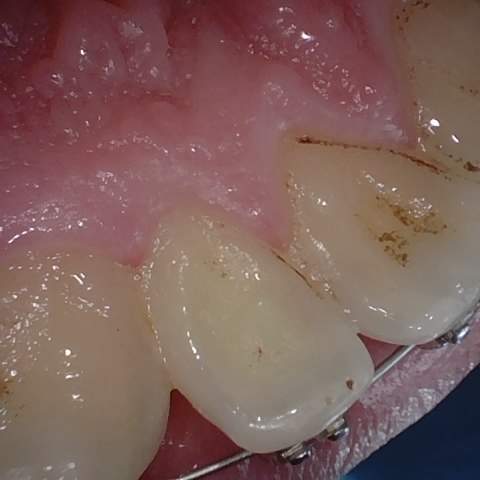

Annotated as "Good"